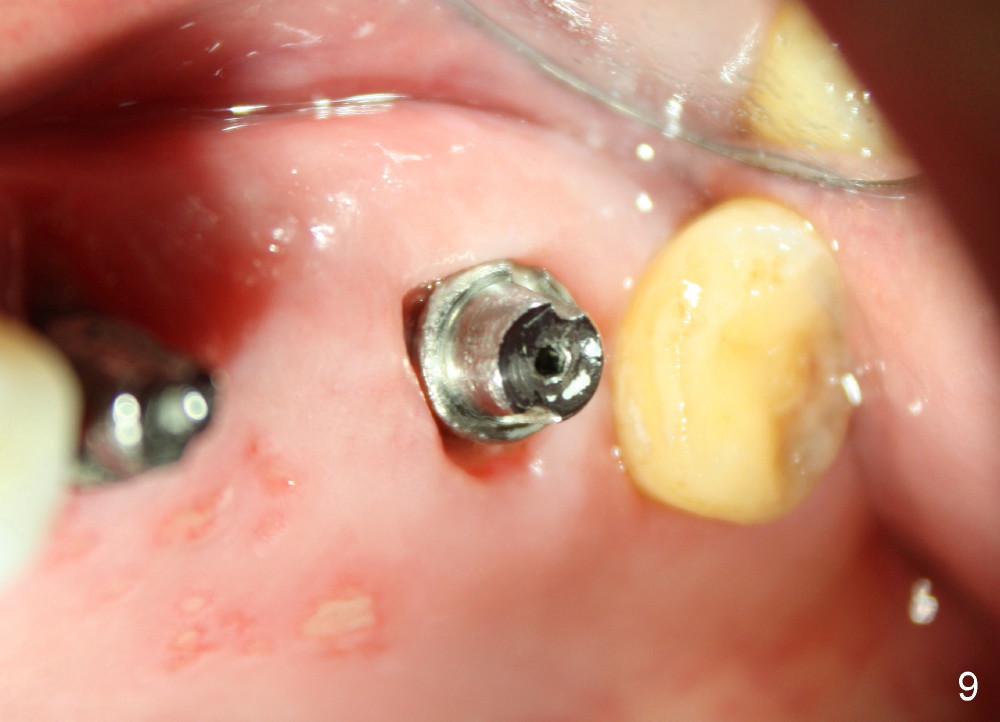

A 84-year-old man has a failing bridge.  A short implant was placed at the pontic site 5 months ago (Fig.1, taken 2 months postop).  The bridge was temporarily recemented.  It is planned at next appointment to extract #13, uncover the implant at pontic and save #15 if possible.  When the bridge is removed, the tooth #15 is also found non salvageable (Fig.2). The root stump of #15 is oval, 5x10 mm.  Preop PA shows that the 2nd molar has two roots (Fig.1: *).  When the tooth is extracted, the septum is found wide buccolingually (Fig.3: S, between the buccal (B) and palatal (P) sockets).  Osteotomy is formed in the septum with combination of drills and osteotomes, followed by insertion of taps (Fig.4).  Finally the osteotomy (Fig.5 O) in the septum (S) of #15 deviates into the buccal (B) socket.  When the implant is placed (Fig.6), it deviates buccally slightly (Fig.7).  The remaining sockets are filled by bone graft (Fig.7 G).  Immediate provisional bridge is fabricated after placement of abutments (A).  The main purpose of the provisional at early stage is to hold bone graft in place.  There is no occlusal contact with the opposing dentition,  Due to time constraint, the uncovering of #14 is postponed.  The provisional dislodges 2-3 days postop.  The patient returns for recementation 5 days postop; the sockets have initially healed (Fig.8,9, as compared to Fig.7).